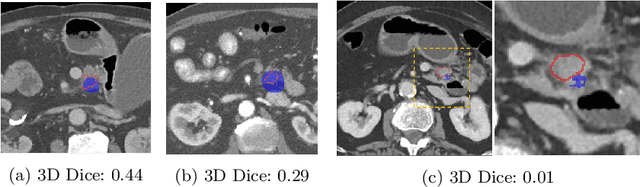

Abstract:Pancreatic cancer is one of the global leading causes of cancer-related deaths. Despite the success of Deep Learning in computer-aided diagnosis and detection (CAD) methods, little attention has been paid to the detection of Pancreatic Cancer. We propose a method for detecting pancreatic tumor that utilizes clinically-relevant features in the surrounding anatomical structures, thereby better aiming to exploit the radiologist's knowledge compared to other, conventional deep learning approaches. To this end, we collect a new dataset consisting of 99 cases with pancreatic ductal adenocarcinoma (PDAC) and 97 control cases without any pancreatic tumor. Due to the growth pattern of pancreatic cancer, the tumor may not be always visible as a hypodense lesion, therefore experts refer to the visibility of secondary external features that may indicate the presence of the tumor. We propose a method based on a U-Net-like Deep CNN that exploits the following external secondary features: the pancreatic duct, common bile duct and the pancreas, along with a processed CT scan. Using these features, the model segments the pancreatic tumor if it is present. This segmentation for classification and localization approach achieves a performance of 99% sensitivity (one case missed) and 99% specificity, which realizes a 5% increase in sensitivity over the previous state-of-the-art method. The model additionally provides location information with reasonable accuracy and a shorter inference time compared to previous PDAC detection methods. These results offer a significant performance improvement and highlight the importance of incorporating the knowledge of the clinical expert when developing novel CAD methods.